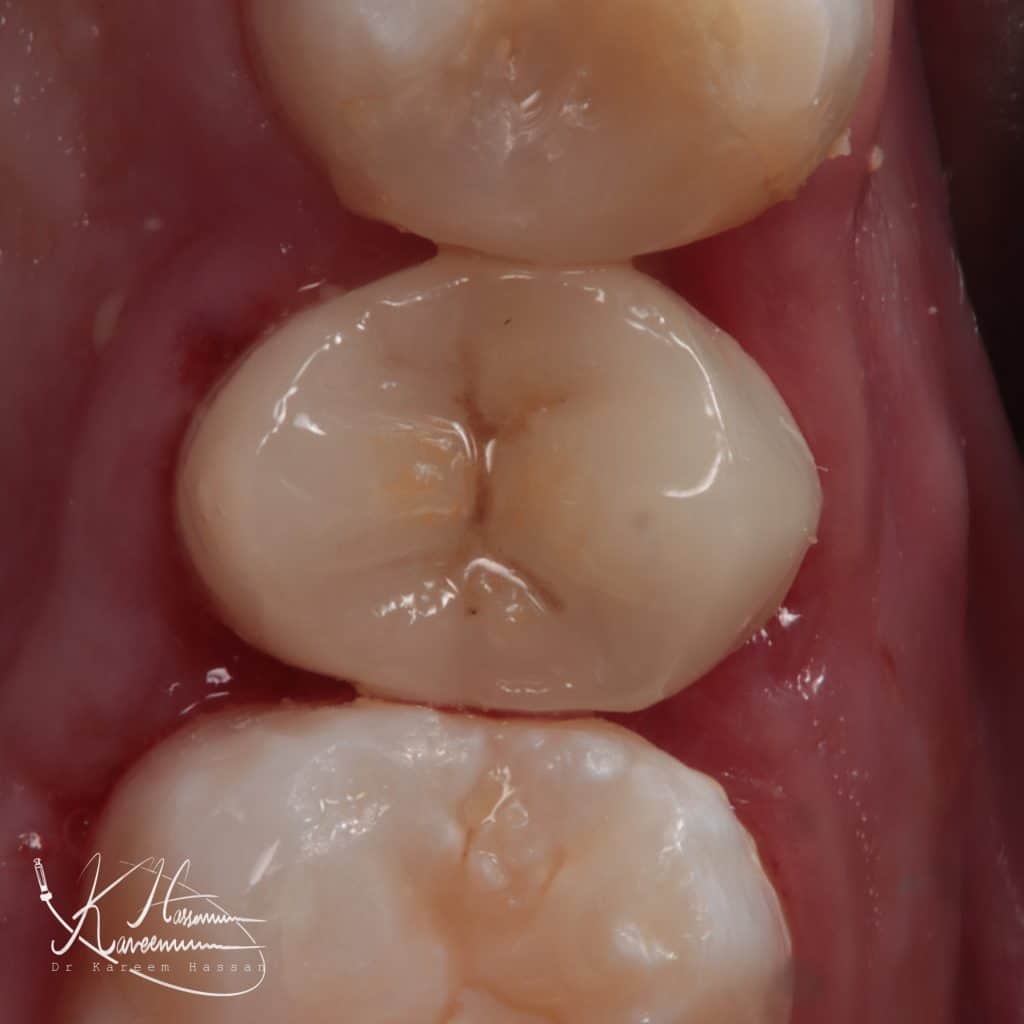

E-Max overlay

Cementation with heated composite AP-X

Immediate result

Another view